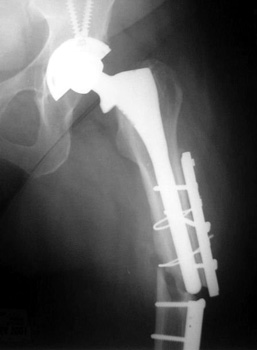

Side plate placed for periprosthetic fracture, now broken with loss of reduction of femur fracture

6/97

11/02